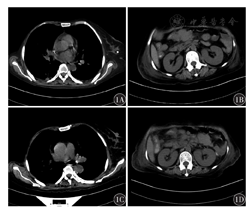

患者既往有高血压病史8年,血压最高达160/100 mmHg(1 mmHg=0.133 kPa);脑梗死半年,左侧肢体活动稍不便。诊断为DLBCL,Ann Arbor分期Ⅲ期B组,非生发中心型,三次打击淋巴瘤;重度贫血;高血压3级(极高危);脑梗死后遗症。2020年11月5日接受1个疗程R2-CHOP方案治疗,具体为来那度胺25 mg,每日口服,第1天至第14天;利妥昔单抗375 mg/m2,静脉注射,第0天;环磷酰胺750 mg/m2,静脉注射,第1天;表柔比星70 mg/m2,静脉注射,第1天;长春地辛4 mg,静脉注射,第1天;地塞米松15 mg,静脉注射,第1天至第5天。服用来那度胺10 d后Plt降至33×109/L,WBC降至0.49×109/L,遂停用。2020年11月22日胸部CT示:双肺条索影,双侧胸膜增厚,右侧乳腺组织缺如;左乳钙化灶(图1A);全腹部CT示:回肠部肿瘤切除并小肠造瘘术后改变,腹盆腔多发占位,腹腔脂肪间隙模糊,胆囊炎,脾脏低密度灶,腹腔小淋巴结(图1B)。2020年11月24日行1个疗程R2-ECHOP(R2-CHOP方案+依托泊苷)方案化疗,加依托泊苷100 mg/m2,静脉注射,第1天至第3天。8 d后Plt降至19×109/L,WBC为1.06×109/L,再次停用来那度胺。2020年12月21日胸部CT示:两肺下叶炎性改变,右肺新增小结节,双侧胸膜增厚,右肺胸腔少量积液,心包积液,右侧乳腺组织缺如;左乳钙化灶,甲状腺左叶钙化灶(图1C);全腹部CT示:腹盆腔多发占位伴局部渗出,胆囊炎,脾脏低密度灶,胰头增大,盆腔少量积液(图1D)。化疗期间患者出现骨髓抑制,予输注红细胞、血小板、粒细胞集落刺激因子(G-CSF)、血小板生成素(TPO)等对症处理。2次化疗后,患者颈部、肺门及纵隔淋巴结缩小,其余各处淋巴结未见增大。